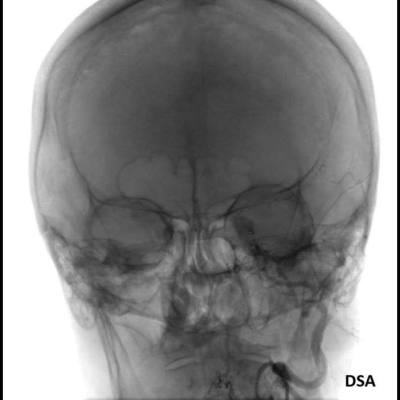

- C) DSA incelemelerinde sol eksternal karotid arter (ok) kateterizasyonunda kontrast maddenin kavernöz sinüse (ok) geçtiği izleniyor. Tedavi sonrası görüntüde kavernöz sinüs ile karotis arteriyel sistem arasında bulunan fistül traktına coil embolizasyon (ok) işlemi uygulandığı görülüyor.

- DSA: Fistülün akış hızını karakterize ederek direkt ve indirekt fistülleri net olarak ayırabilir. ICA defektinin tam anatomik yerini ve ICA veya ECA dural besleyicilerini gösterir. Ayrıca DSA ile endovasküler tedaviler yapılabilmektedir.

- Olgumuzun DSA incelemelerinde sol ICA ve ECA’dan kavernöz sinüse fistülöz bağlantı olduğu izlenmiş ve coil embolizasyon işlemi uygulanarak tedavi edilmiştir.